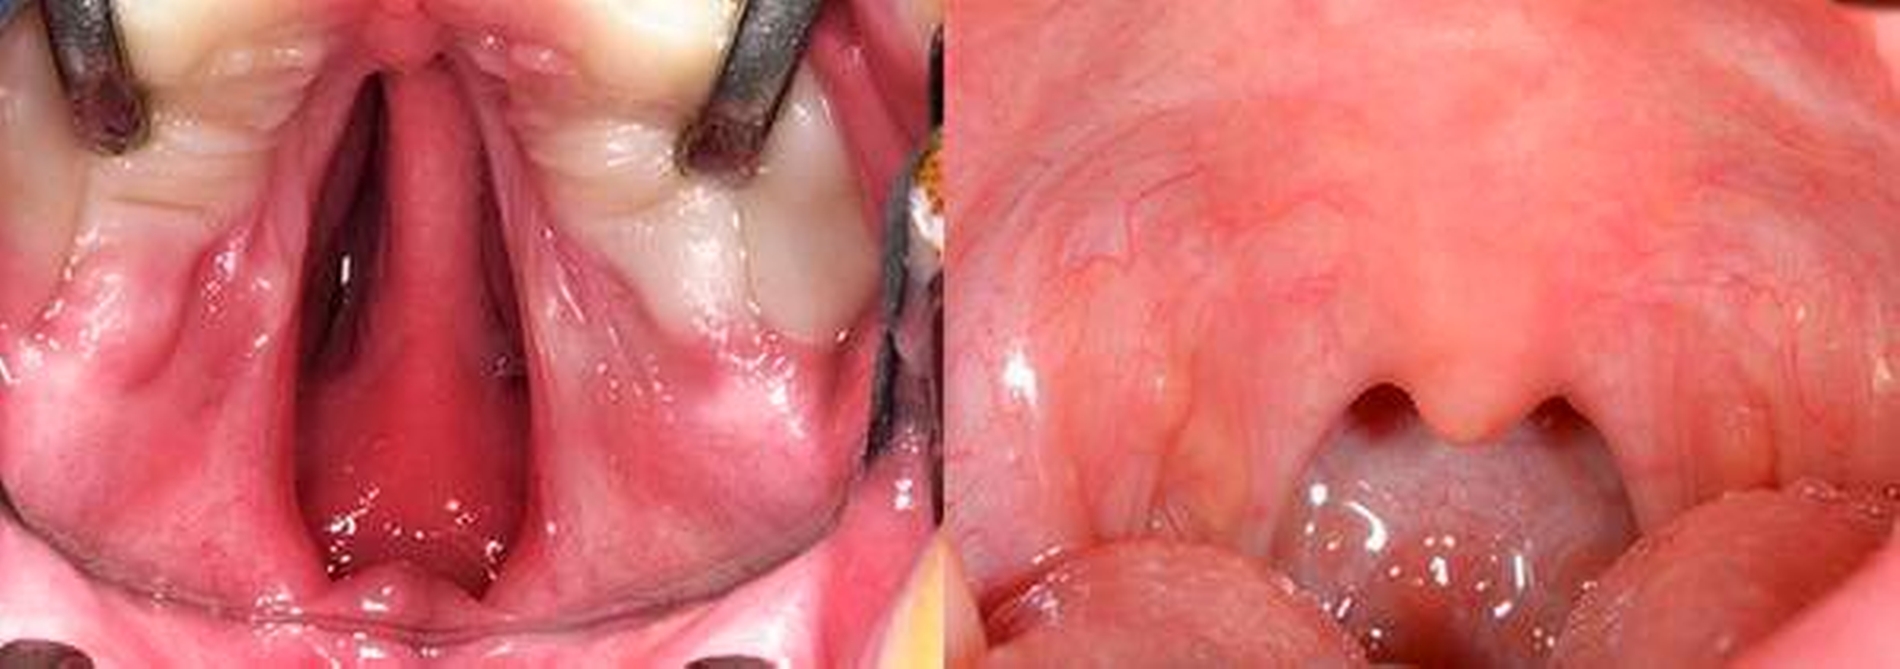

Für die Gaumenspaltplastik wurden verschiedene Modifikationen beschrieben, die meist auf den Prinzipien der Brückenlappenplastik nach Langenbeck/Ernst/Veau/Axhausen und der Stiellappenplastik nach Veau beruhen. Entscheidend für das funktionelle Ergebnis ist die Wiederherstellung der Muskelfunktion eines ausreichend langen weichen Gaumens. Wir führen die intravelare Veloplastik nach Kriens mikroskopisch assistiert in der Modifikation der radikalen Muskeldissektion nach Sommerlad durch (Abbildung 5). Isolierte Gaumenspalten werden immer einzeitig verschlossen, bei einseitigen Totalspalten erfolgt der Gaumenverschluss meist in zwei Schritten, so dass in jedem Fall mit etwa drei Jahren die Primärbehandlung abgeschlossen ist. Durch die Veloplastik tritt bei einseitigen Totalspalten eine Verschmälerung der Spalte des harten Gaumens ein.